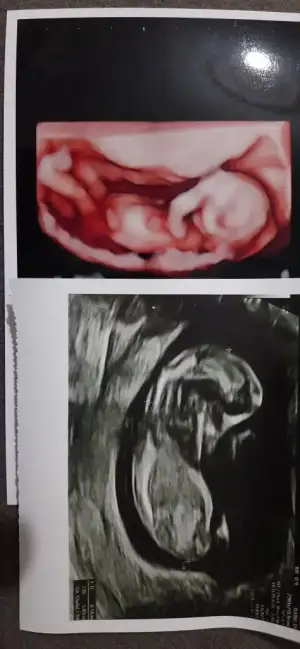

Aynen geçen hafta 13. Haftamdı ve doktorum perinatolog beyin lobları, kalbi, kalbin etrafını saran yapı, damarları, parmakları, midesi, damakları, dudakları her şeyi tek tek incelendi. Neredeyse omurunu ve kaburgalarını bile tek tek sayacaktı. Bu haftalar kontrol için cidden önemli ki görüşmenin sonunda ‘işte şimdi sevinip kutlayabilirsiniz’ dedi. Sonra da nifty için kan verdim salı kontrolüm var o zamana kadar sonuç da gelmiş olacak, inşallah o da iyi gelir ve ben birkaç gece de olsa huzurlu uyurum